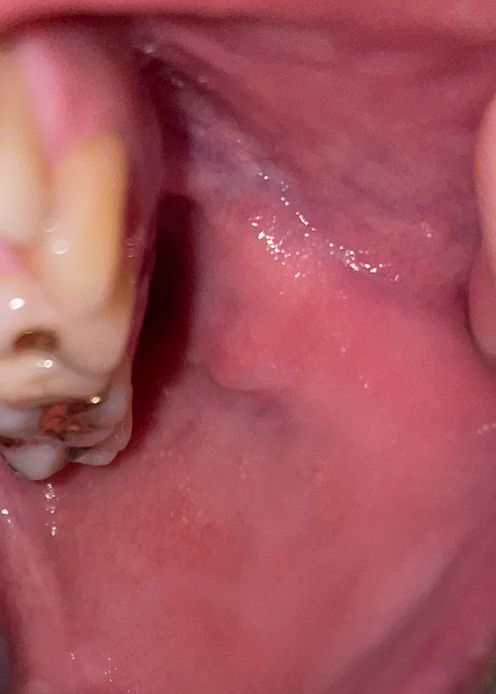

구강 볼 안쪽 점막에 하얀 돌기들과 통증은 어떤 질병인가요?

따끔 거리고 화끈거리는 통증이 있는데 이게 편평태선이라는 질병인지 홍반증인지 궁금합니다 없어지지 않고 있는데 냅둬도 되는 건가요 구강암으호 변하는 질병은 아니겠죠? 왼쪽 볼에만 있습니다 혹시나 잘때 이갈이 장치를 착용하는디 그거때문에 생긴 건가요?

• 2번 째 사진

하얀 돌기와 통증이 있는 증상은 여러 가지 원인에 의해 발생할 수 있습니다만, 장치를 새로 착용하게 된 경우, 구강 점막에 자극이 가해져 증상이 발생했을 가능성이 있습니다.

구강암은 일반적으로 증상이 호전 없이 지속되는 양상을 보이기 때문에, 증상이 2주 이상 지속된다면 구강내과 진료를 제공하는 치과에서 진료를 받아보시는 것이 좋겠습니다.